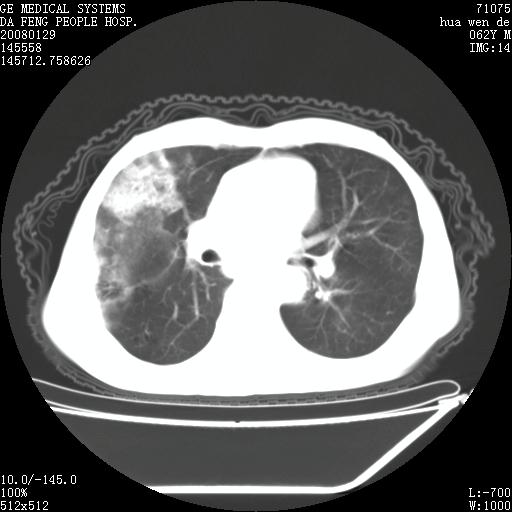

男性,67岁。作肺部检查时发现

理由:1、右上肺内病灶,空洞形成,有液平。

2、肺内多处炎症。

3、前段肺内炎症,支气管引流通畅,与肿块无关系。

1.整个食管扩张,未见明显占位性病变,贲门区亦未见明显占位病变,考虑:贲门失驰缓症;

2.右上肺病变边缘可见毛刺,囊壁厚度不均匀,周围境界较清楚,未见炎性渗出性影,右上肺外带可见片状影,边缘不清,考虑:肺癌伴空洞形成、右上肺炎。

食管全程扩张,壁均匀不厚,喷门失弛缓症

右上肺空洞可见液平,临近肺野磨玻璃密度,考虑1.结核2.脓肿